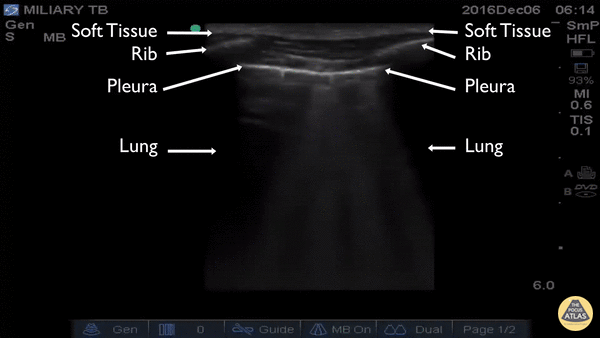

Pulmonary - Miliary TB

The clip was captured in rural Uganda on a patient who presented for weight loss, night sweats, and cough. Utilizing the high-frequency, linear transducer the patient’s thoracic pleura and superficial lung were evaluated. The ultrasound demonstrated multiple focal sub-pleural lesions with tripartite B-lines consistent with miliary tuberculosis. Michael Schick DO, MA Emergency Medicine Physician